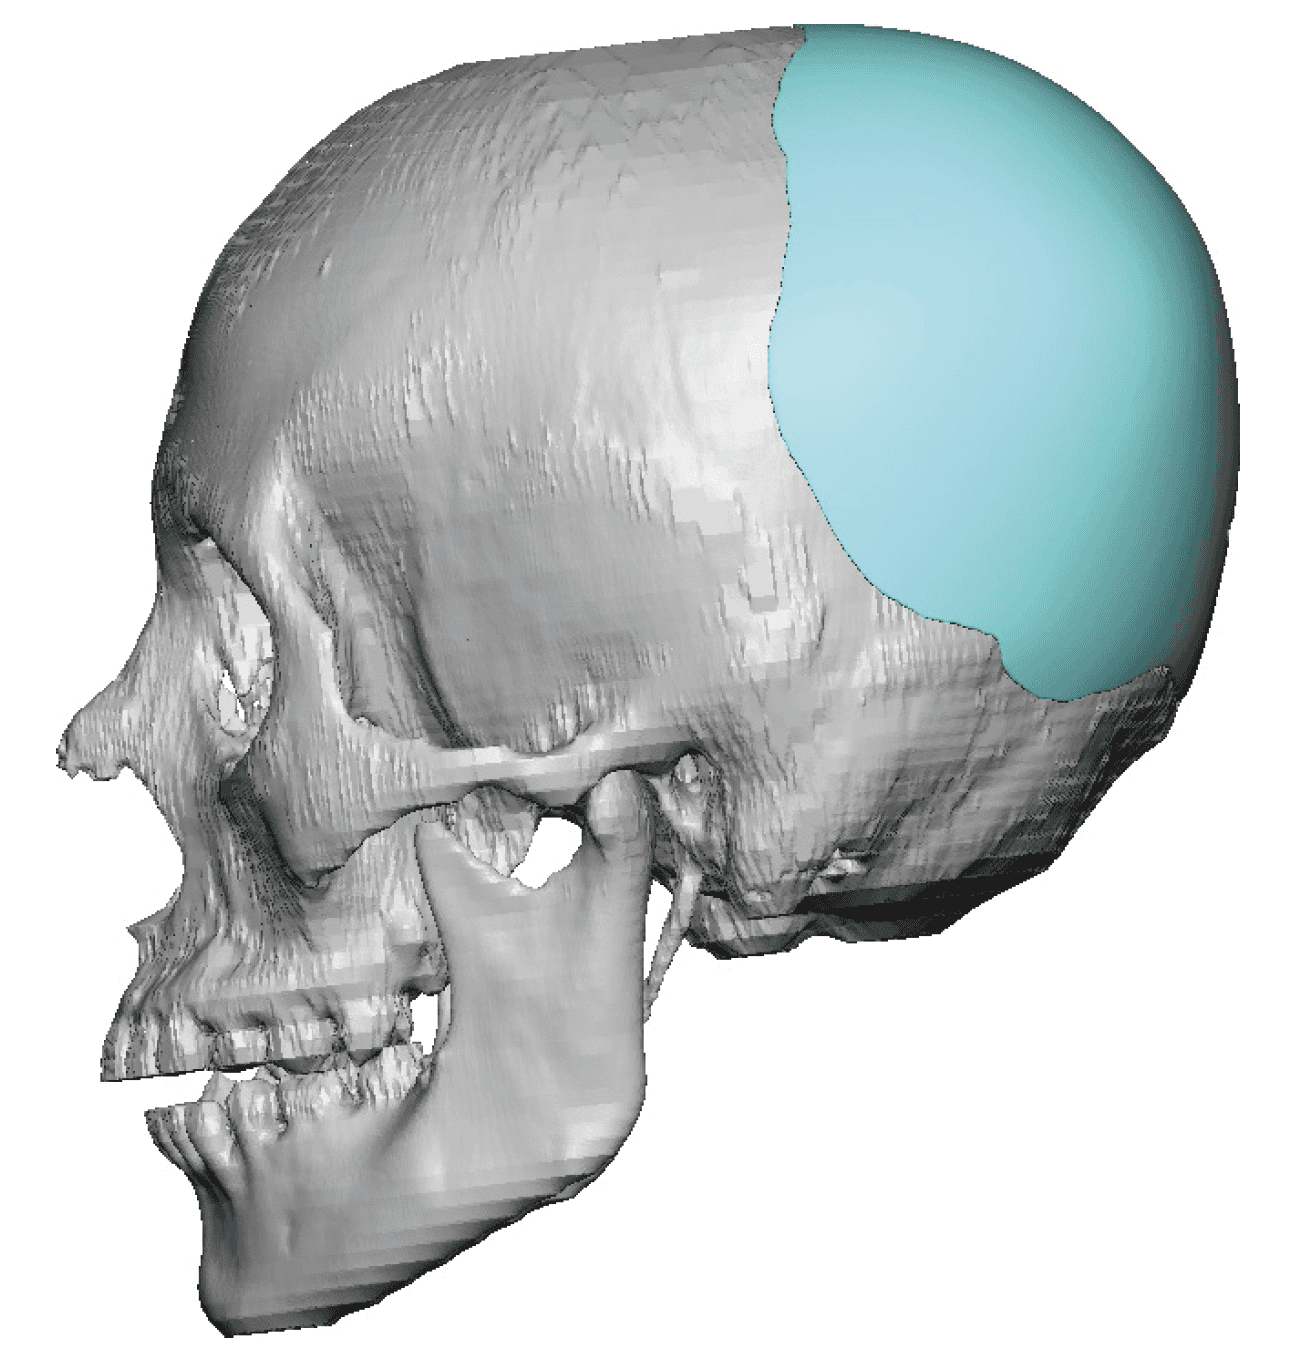

Severe narrowing skull deformity from prior sagittal craniosynostosis repair as an adult.

Complete replacement of entire skull by a custom implant with temporal fat injections.

Severe narrowing skull deformity from prior sagittal craniosynostosis repair as an adult.

Complete replacement of entire skull by a custom implant with temporal fat injections.